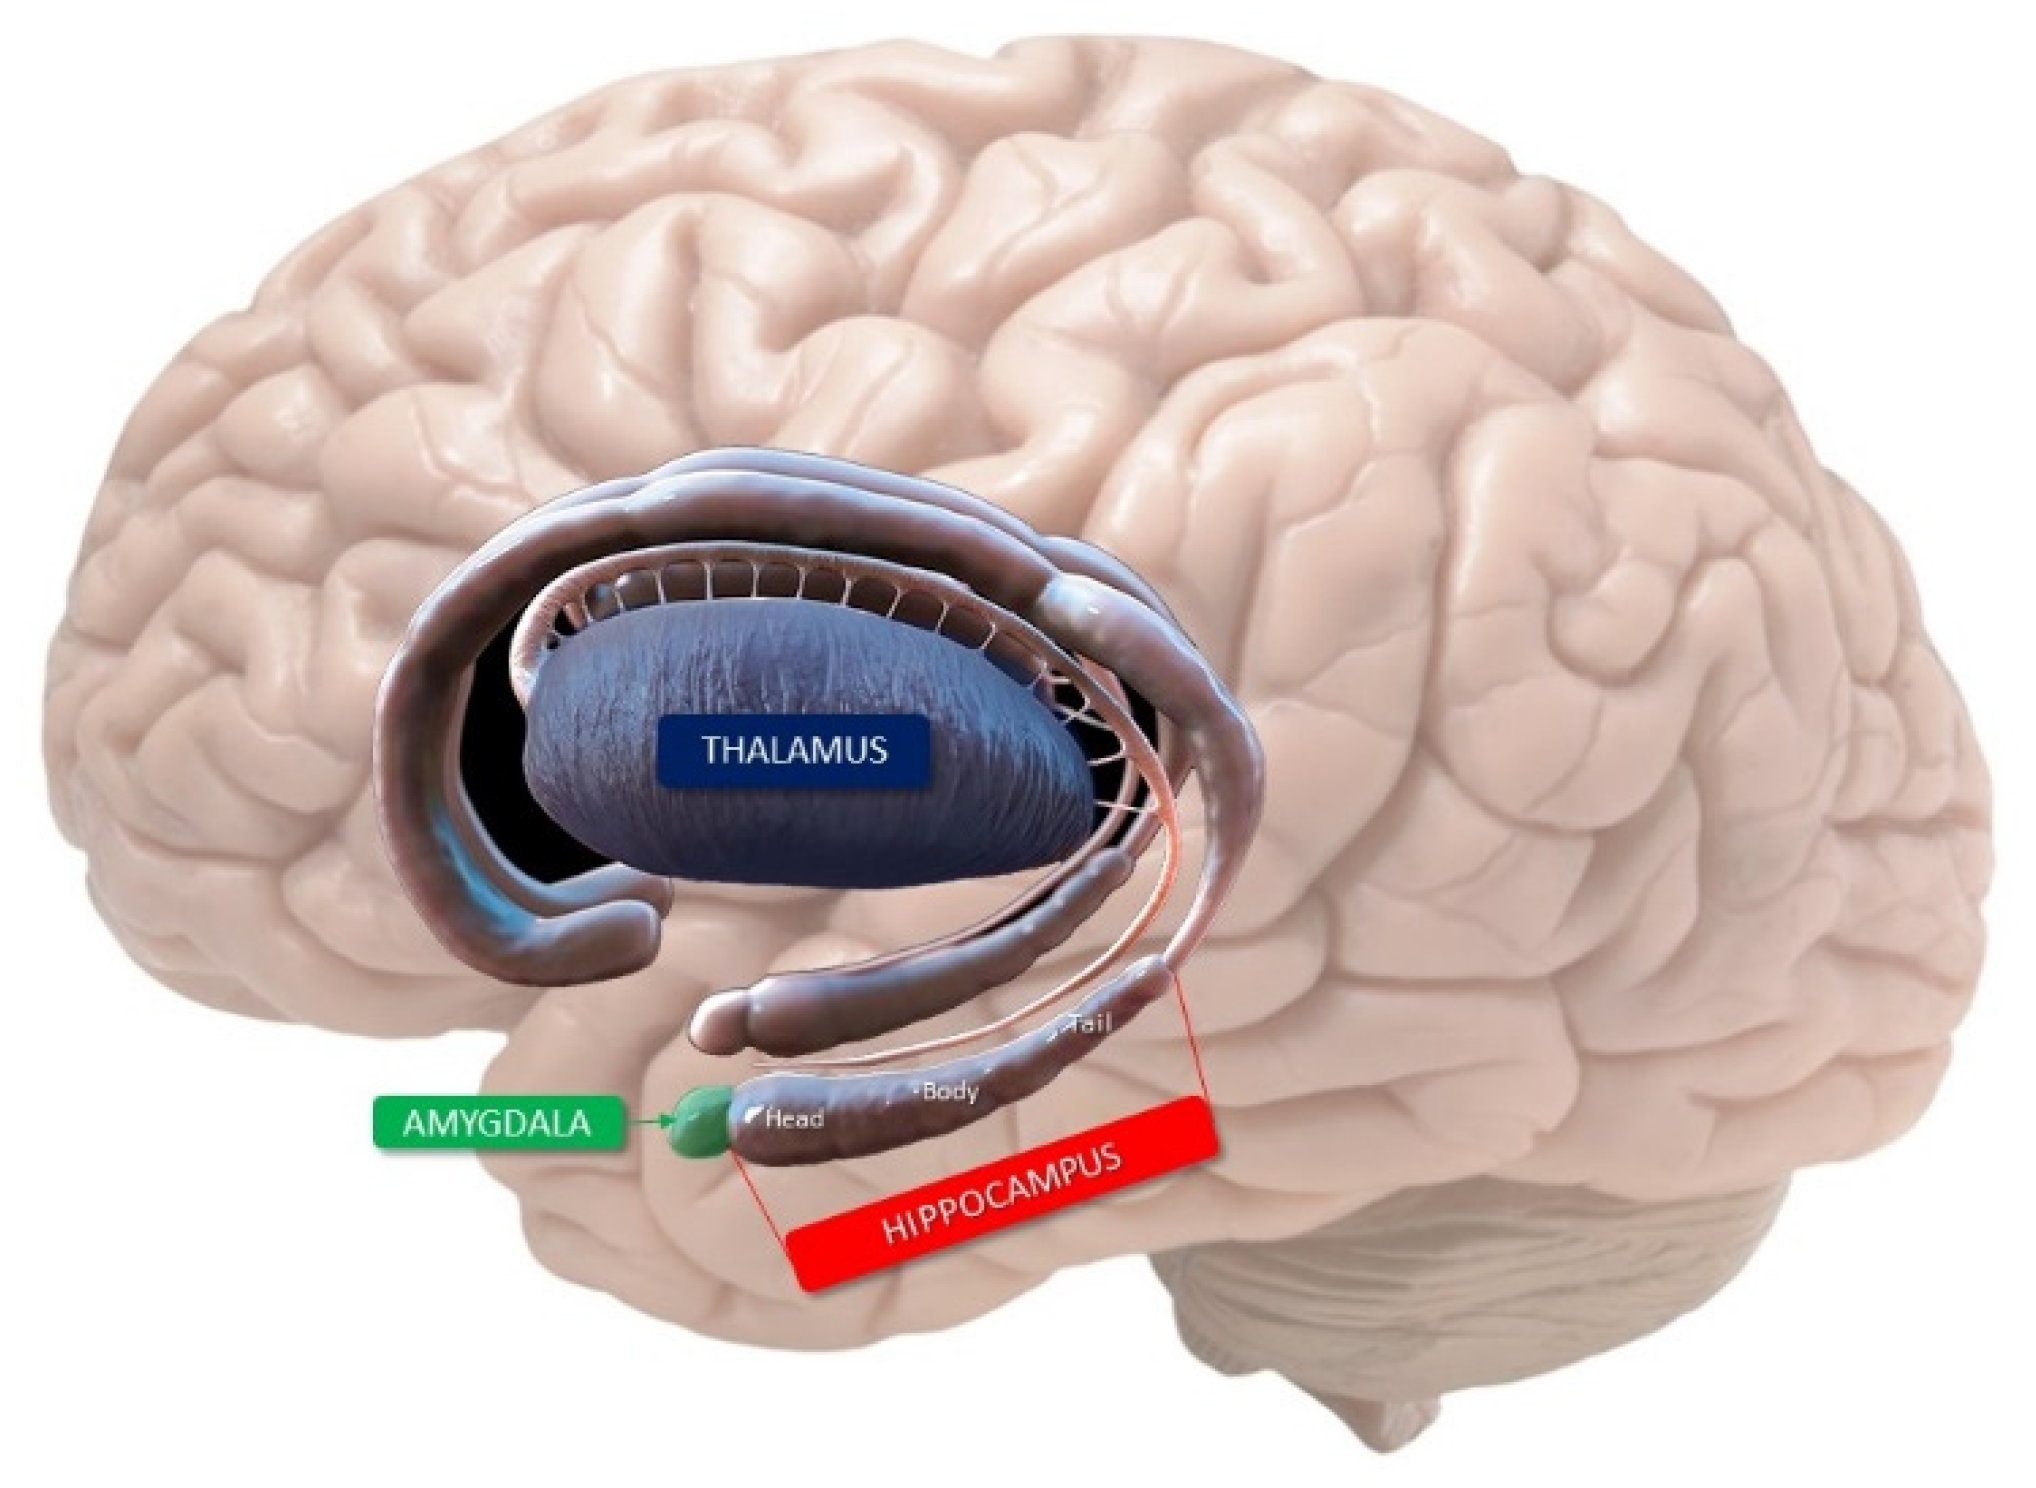

2. Anatomy of the Hippocampus

4. Mnemonic Functions of Hippocampus

- The polysynaptic pathway composes the following circuit: parietal, temporal, and occipital cortex → entorhinal cortex → dentate gyrus → CA3→ CA1→ subiculum → alveus → fimbria → fornix → mammillothalamic tract → anterior thalamus → posterior cingulated → retrosplenial cortex.

- The direct intra-hippocampal pathway is activated by afferent input from the temporal association cortex through the perirhinal and entorhinal area to CA1; from there, efferent projections reach the inferior temporal cortex, temporal pole, and prefrontal cortex through the subiculum and entorhinal cortex.